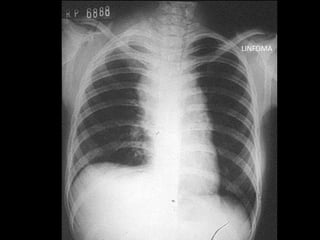

LINFOMA

LINFOMAS

• Ubicación: mediastino medio y anterior

• Clínica: poca, en general neurohumoral

• Variedades:

– Hodgkin

– No Hodgkin

• Diagnóstico: mediastinostoía, mediastinoscopía, VATS

• Tratamiento: QTX + RTX

LINFOMAS • Ubicación: mediastinomedio y anterior • Clínica: poca, en general neurohumoral • Variedades: – Hodgkin – No Hodgkin • Diagnóstico: mediastinostoía, mediastinoscopía, VATS • Tratamiento: QTX + RTX